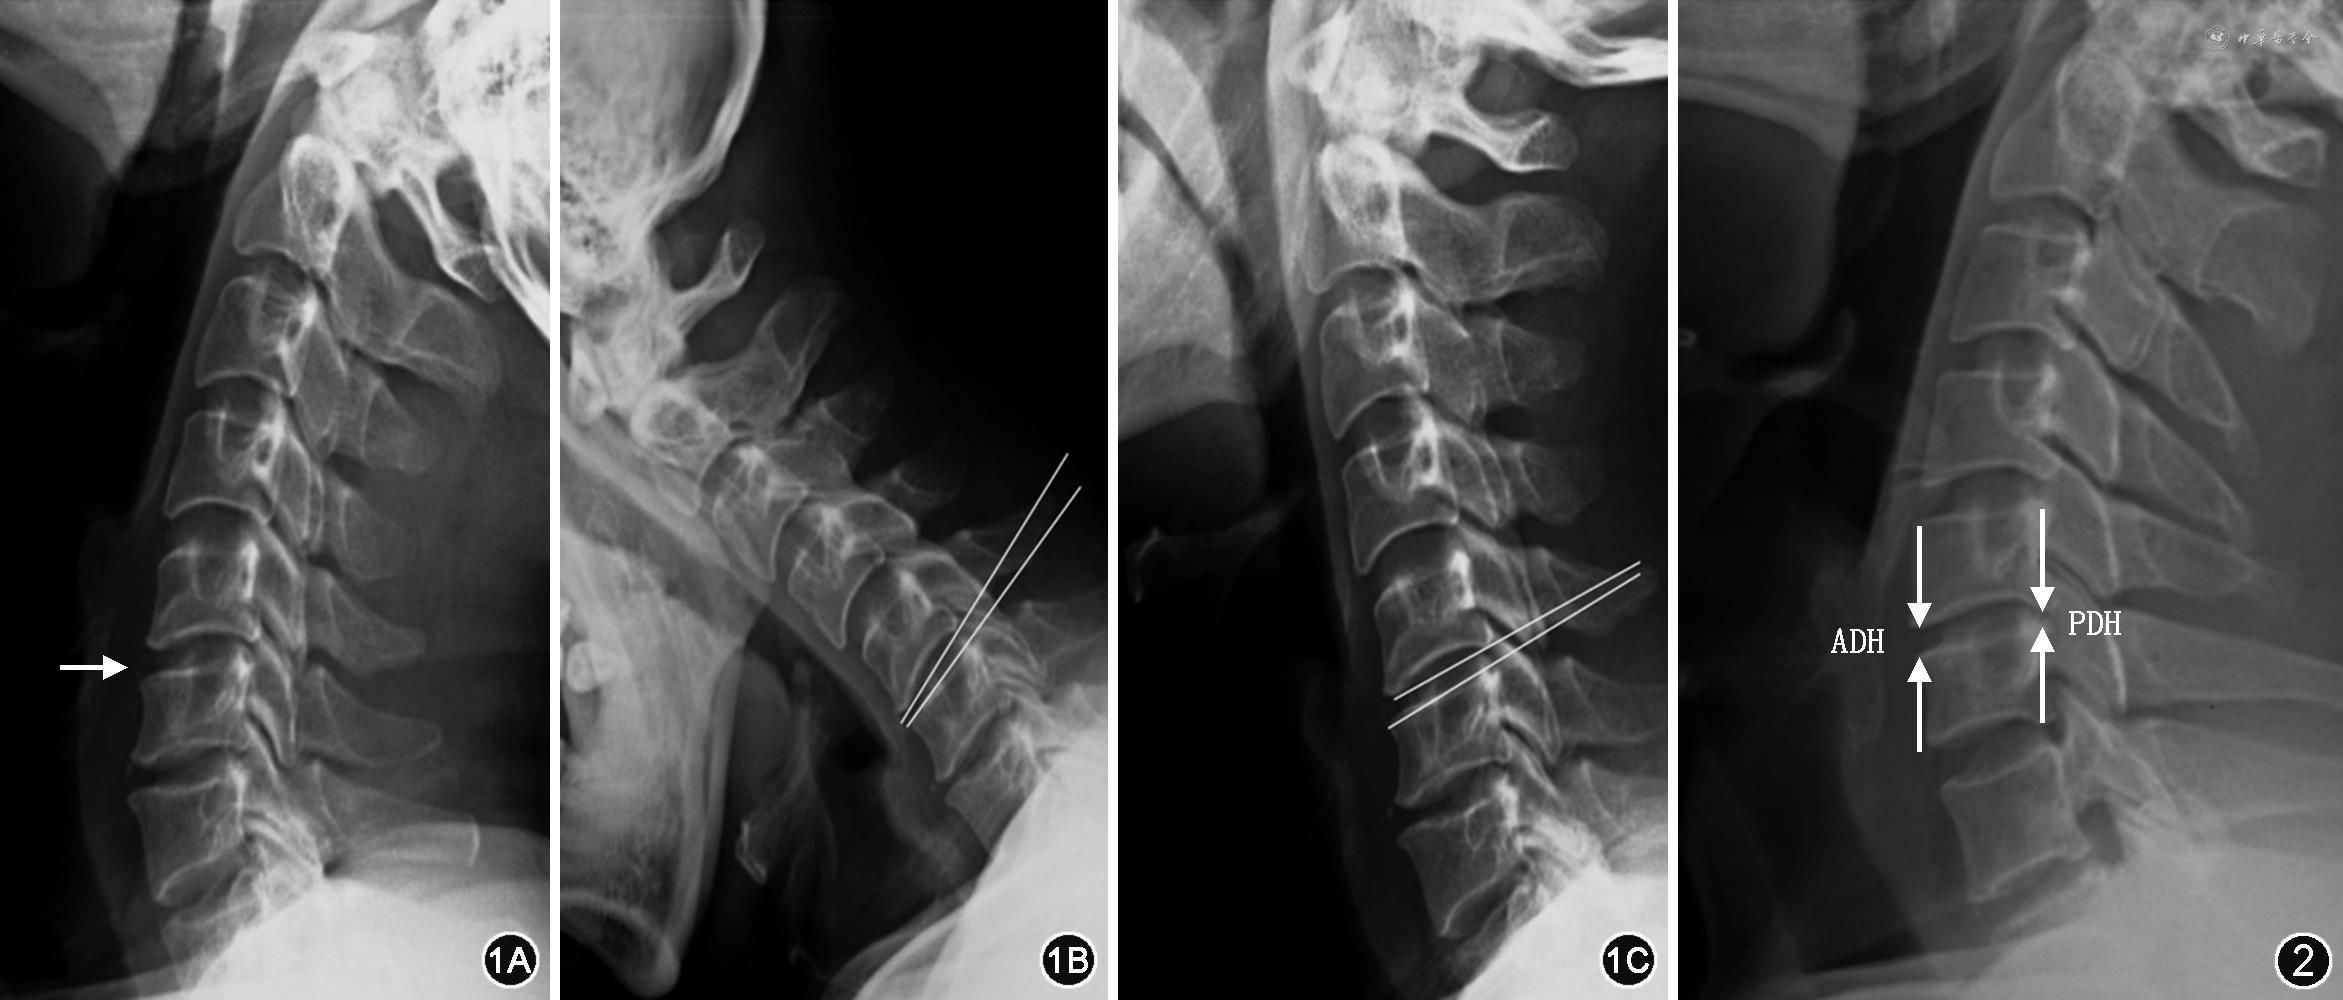

1.影像学评估:(1)使用侧位X线片,分别于术前及末次随访时在颈椎过屈过伸位X线片上测量并计算手术节段活动度(ROM)。手术节段ROM具体为上位椎体下终板和下位椎体上终板连线夹角在过伸位和过屈位的差值(图1)。将患者根据文献[10]分为活动度较差组A组(≤7°)和活动度较佳组B组(>7°)。术前椎间隙高度为中立位X线片上拟置换节段椎间隙上下终板最前缘和上下终板最后缘距离之和的平均值(图2)。在本次研究中,笔者认为,术后长期随访时进入活动度较佳组的患者为更适合接受ACDR术的患者,即更符合ACDR术适应证。(2)术前在颈椎CT及过屈过伸位X线片上评估椎旁骨化(PO)的分级[11]。具体分级标准为0级:无骨化;1级:存在未侵入椎间隙的骨化;2级:存在侵入椎间隙的骨化;3级:存在相邻椎体间形成桥接的骨化,且影响手术节段活动度;4级为完全融合,且手术节段活动度丧失。